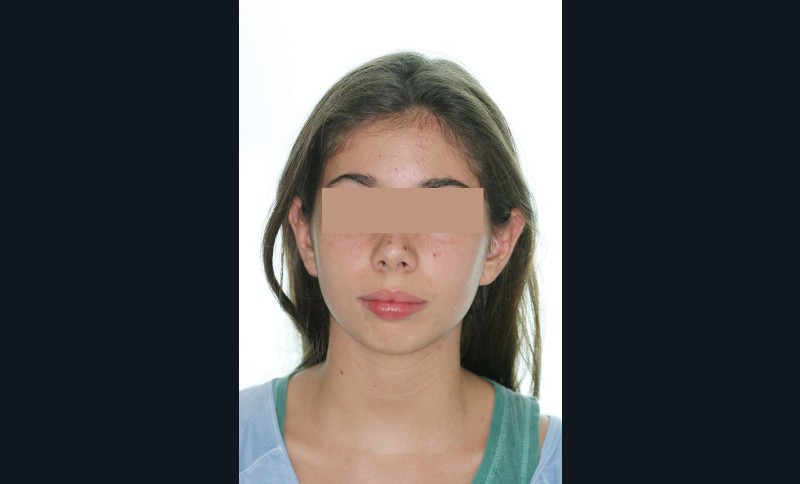

Nous sommes en présence d’une patiente adolescente âgée de 12 ans ½ dans une phase de croissance faciale favorable.

Elle présente une classe II squelettique par rétrognathie mandibulaire et une classe II dentaire molaire et canine droite et gauche associée à une biproalvéolie incisive maxillaire et mandibulaire.

L’environnement vertical est normodivergent.

Le contexte facial est délicat avec un profil cis-frontal, un angle naso-labial très ouvert et un sillon labio mentonnier marqué avec retour de la lèvre inférieure en arrière des incisives maxillaires.

Le pronostic de correction de la classe II est favorable mais il est très important de souligner la vestibuloversion incisive mandibulaire et le risque parodontal associé (fig. 1 à 3).